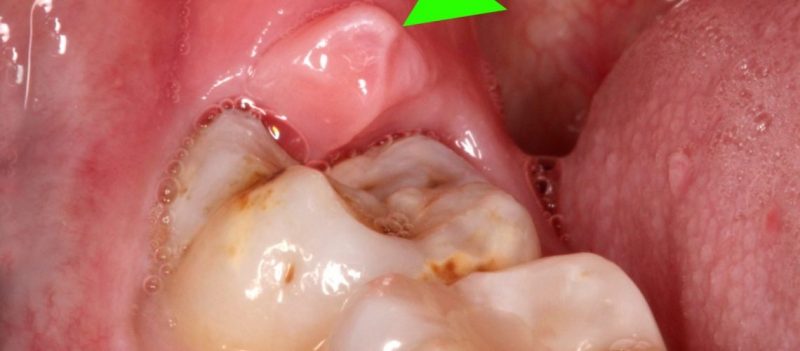

Do răng khôn mọc sau cùng mà vòm miệng của con người thường không có đủ chỗ để chúng mọc bình thường. Do đó, răng khôn mọc lệch, xô lẫn nhau, mọc chen chỗ các răng khác, dẫn đến sưng, đau đớn.

Có nhiều trường hợp gặp phải tình trạng những chiếc răng khôn mọc ngầm, mọc lệch không can thiệp kịp thời, khiến phần nướu răng sưng tấy, dễ tích đọng thức ăn gây hôi miệng, viêm nướu…

Răng khôn mọc còn có thể gây nhiều biến chứng như: viêm nhiễm, đau nhức khi bị mọc răng khôn. Răng khôn mọc lệch, mọc ngầm khiến bệnh nhân sưng, đau nhức trong miệng nên không thể nhai thức ăn.

- Cần nhổ răng khôn khi răng khôn mọc gây các biến chứng đau, u nang, nhiễm trùng lặp đi lặp lại, ảnh hưởng đến các răng lân cận.